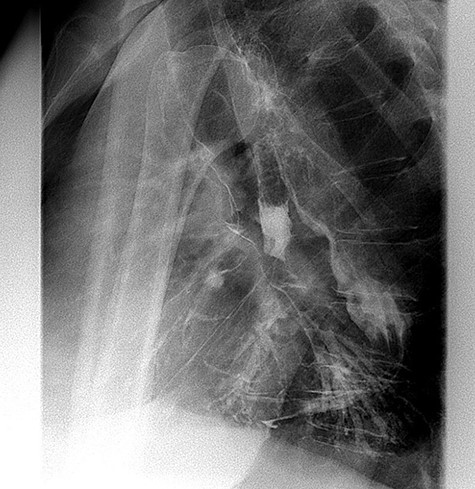

After this endoscopic procedure, the patient was subjected to barium swallow examination that demonstrated the OTSC on the gastric conduit and no filling of the left bronchus (Figure 3), following by complete resolution of symptoms. At the follow-up time of 6 months, the patient is asymptomatic and there is no recurrence of the fistula. To the best of our knowledge, this is the first reported case of GBF treated with OTSC in the literature.

Postoperative barium swallow demonstrating the OTSC on the gastric conduit (white arrow) and no filling of the left bronchus.